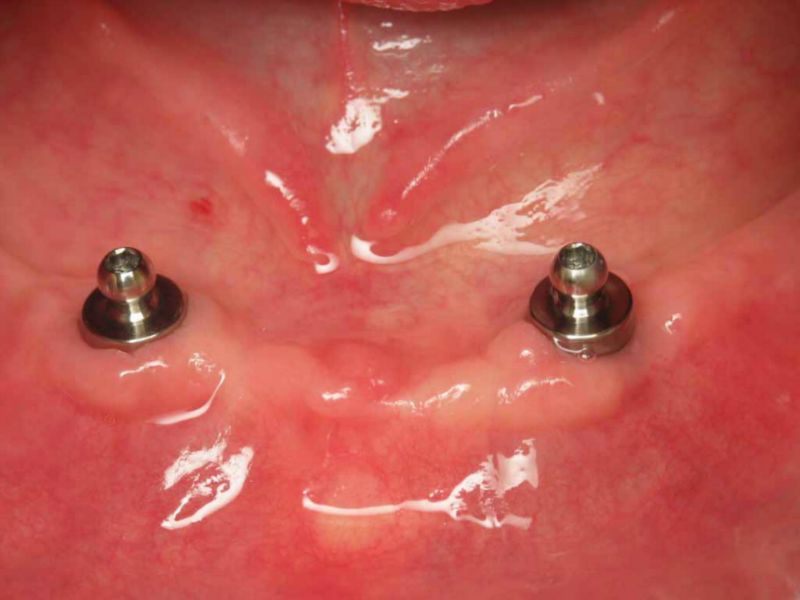

- Boutons-pression à la mandibule

La revue de la littérature scientifique montre que la technique de boutons-pression est à présent considérée comme une option de choix quand il s’agit d’améliorer la rétention d’une prothèse amovible complète à la mandibule, avec comme principaux avantages la simplicité d’exécution et la maintenance réduite par rapport aux barres.

La rétention d’une prothèse sur boutons-pression est aussi efficace que celle procurée par une barre.